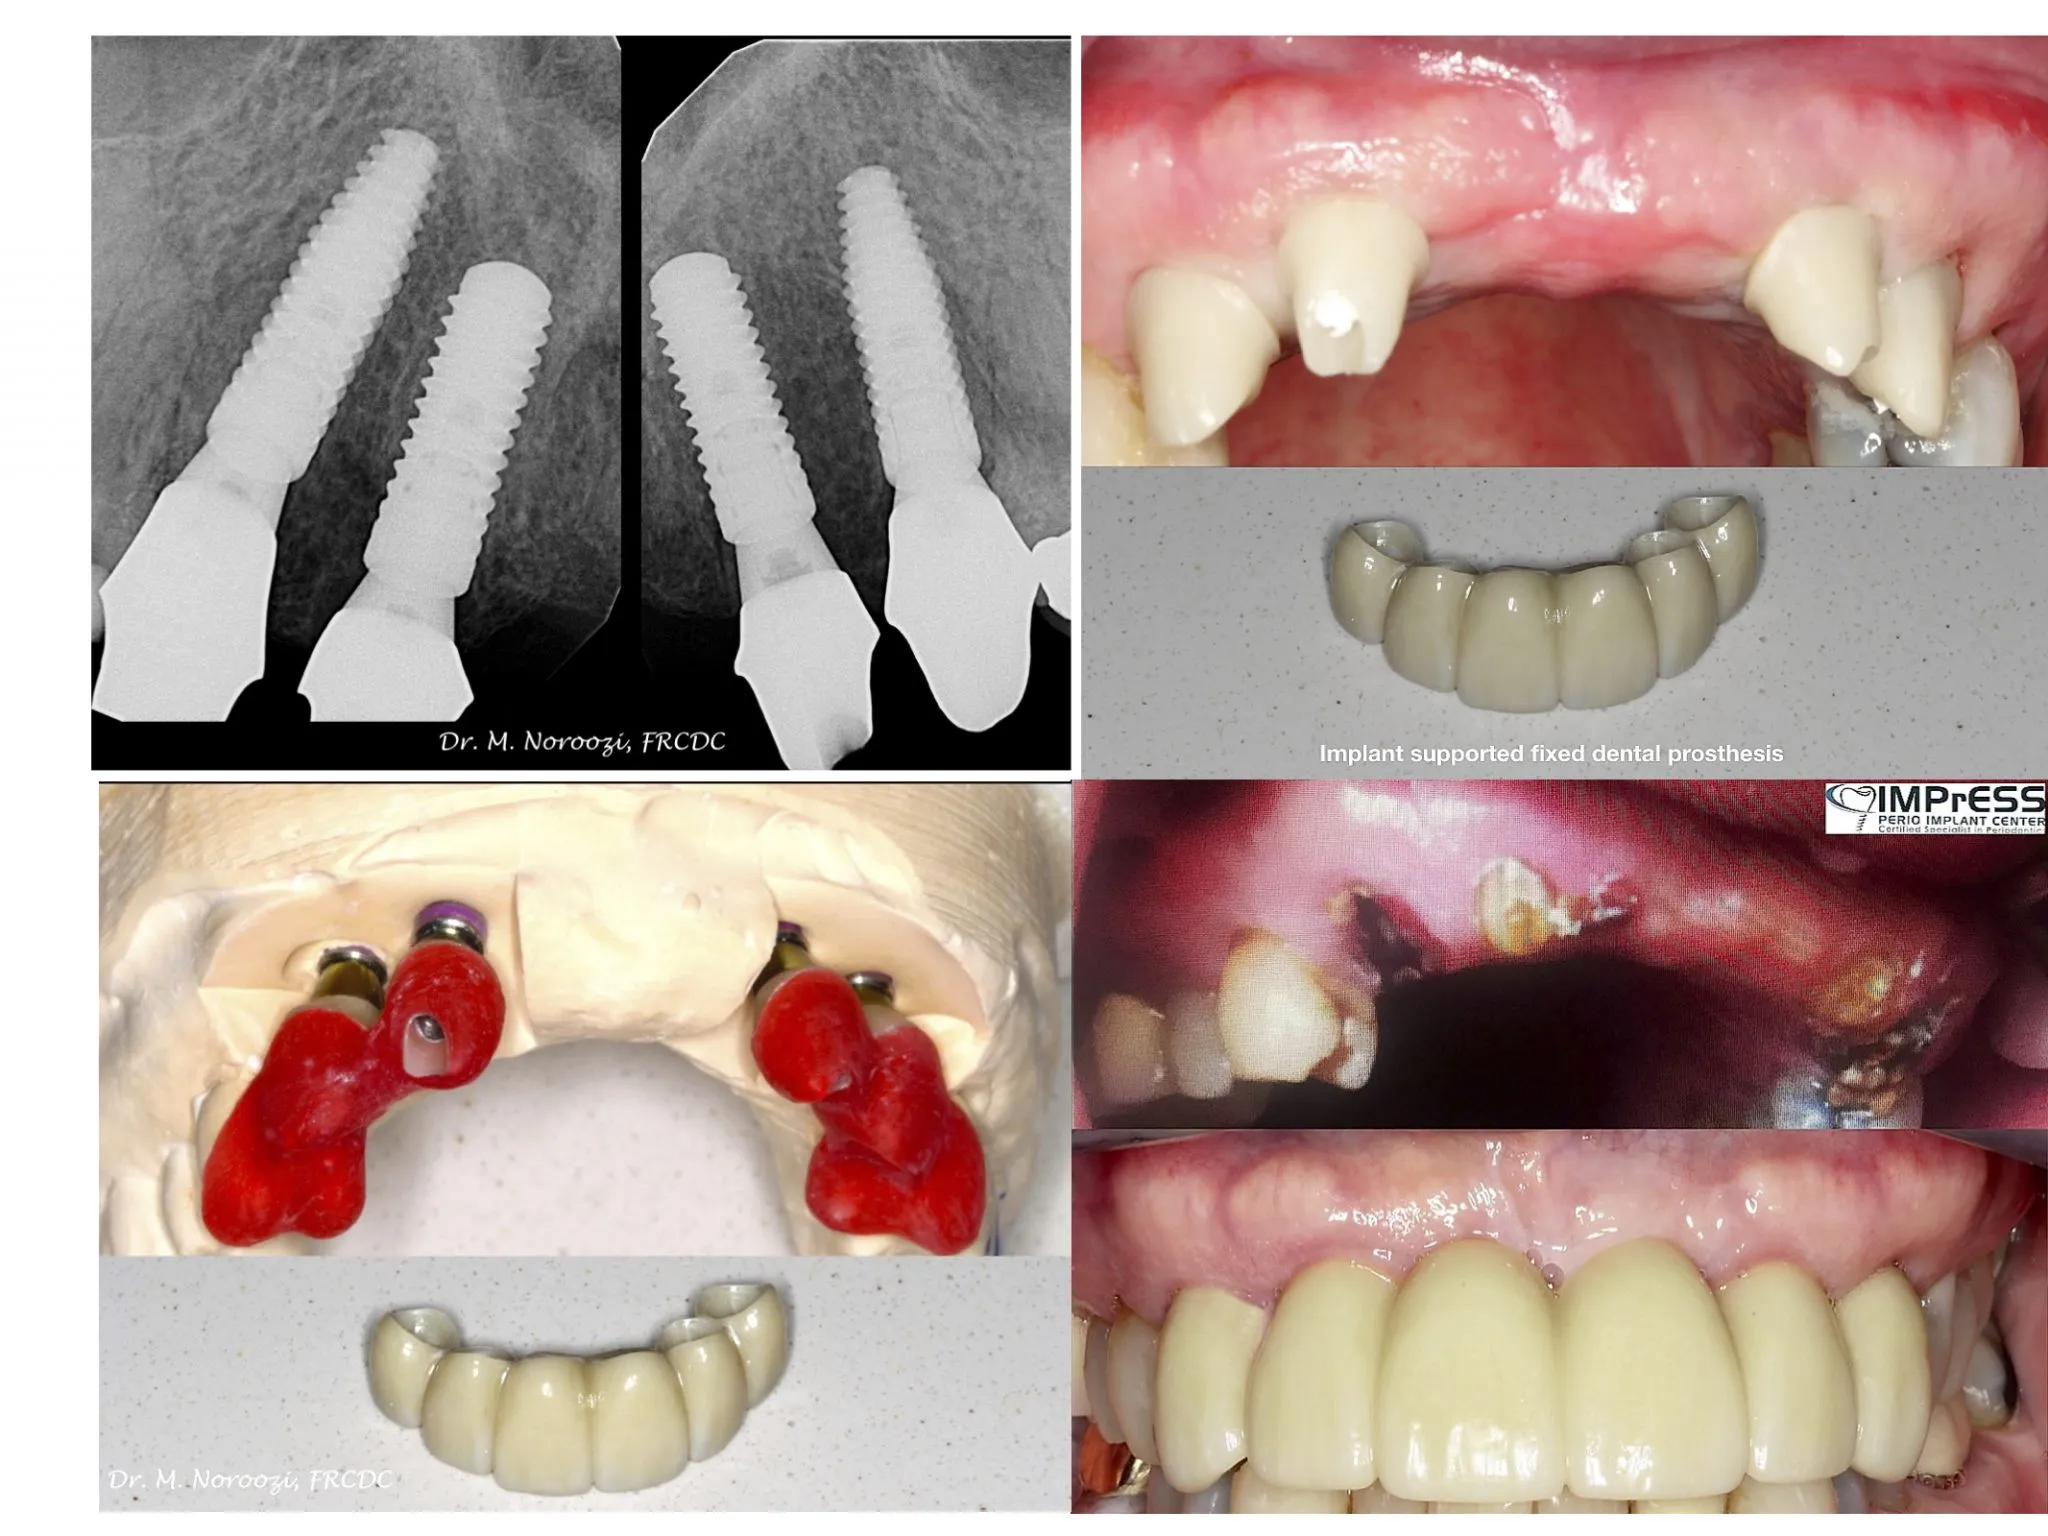

Before & Afters of Dental Implant Patients

Complete Dental Implant Cases Gallery

• During the second stage of surgery and once the tissue is healed, your dentist or specialist will attach an abutment to the implant. An abutment is a post that connects the replacement tooth to the implant. In some cases, the first and second stage of implant surgery may be done in one single stage.

• An artificial replacement tooth is made and your dentist or specialist attaches it to the abutment. It may take several appointments to properly fit the replacement tooth to the abutment.

• When replacing several teeth or all of your teeth, a fixed bridge is anchored to your dental implants. A bridge is a dental restoration that replaces one or more missing teeth by spanning an area that has no teeth. The bridge is held firmly in place by dental implants on each side of the missing tooth or teeth.

General Disclaimer: The results in the photographs are examples only and do not imply any certainty of the result of a procedure, and all outcomes are subject to the circumstances of the individual patient.